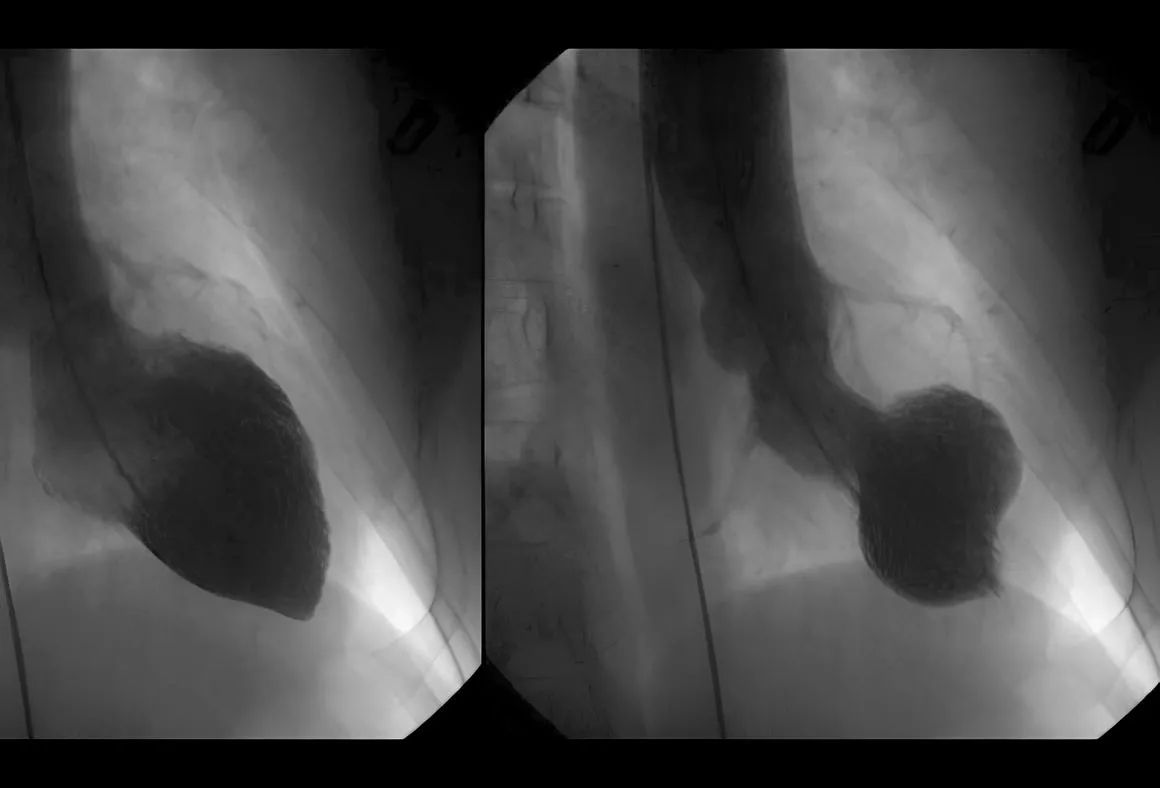

Цікаво, що такоцубо - це не прізвище вченого, а японська назва пастки для восьминогів. Таку ж форму має один зі шлуночків серця людини за наявності синдрому розбитого серця (це можна побачити, скажімо, на УЗД).